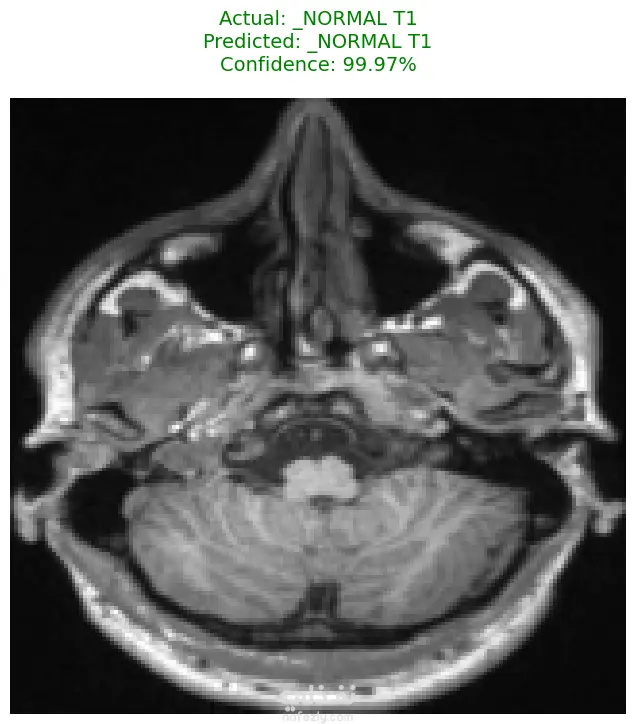

الوصف: قمت بتطوير نموذج تعلم عميق (CNN) قادر على التمييز بين 27 فئة مختلفة من الأورام والحالات الطبيعية بدقة تصل إلى 93%. شمل المشروع مراحل معالجة البيانات الضخمة، تنظيفها وموازنتها، وتصميم معمارية مخصصة لضمان الكفاءة العالية وتقليل استهلاك الذاكرة. المميزات التقنية: دقة استثنائية: حقق النموذج دقة تصل إلى 93% على بيانات التحقق (Validation Accuracy). معالجة البيانات الضخمة: تم العمل على قاعدة بيانات ضخمة، مع تطبيق استراتيجيات موازنة البيانات (Data Balancing) لضمان عدم انحياز الموديل. معمارية مخصصة: تم تصميم شبكة CNN تدعم تقنيات Batch Normalization لتسريع التعلم و Global Average Pooling لتقليل استهلاك الذاكرة وضمان استقرار النموذج. معالجة الصور: استخدام تقنيات OpenCV لقص الصور (Cropping) وإزالة الهوامش غير الضرورية لتركيز الموديل على منطقة الورم فقط. الأدوات والتقنيات المستخدمة: لغة البرمجة: Python. المكتبات الأساسية: TensorFlow / Keras. معالجة الصور: OpenCV & PIL. تحليل النتائج: Scikit-learn (Confusion Matrix & Classification Report). البيئة البرمجية: Google Colab (GPU Acceleration). النتائج المحققة: نموذج قادر على التعرف على أنواع نادرة من الأورام بدقة عالية. تقرير فني يوضح أداء الموديل لكل فئة (Precision & Recall). ملف نموذج جاهز للنشر (Deployment) بصيغة keras الحديثة. يمكنكم الاطلاع على الكود المصدري كاملاً والرسوم البيانية لتقييم أداء النموذج عبر رابط GitHub المرفق، كما يتوفر رابط تحميل النموذج المدرب داخل ملف الشرح.